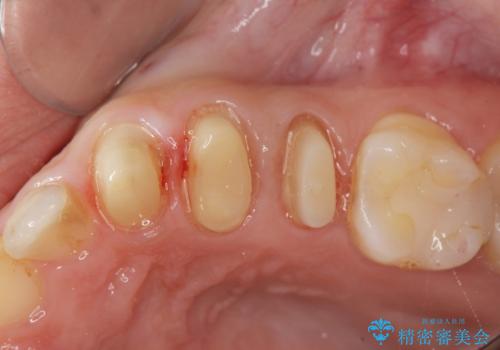

虫歯が大きかったことから、神経の温存はできたものの歯ぐきよりも深い虫歯の問題を解決するため部分矯正治療を併用したセラミック治療を行うこととしました。

当初、歯ぐきよりも深い虫歯のぞんざいや、歯のポジションに問題がありましたがマルチブラケットを用いた部分矯正を行うことで適切な位置へと歯を移動させ、歯周環境を整えたセラミック治療を行うことができました。